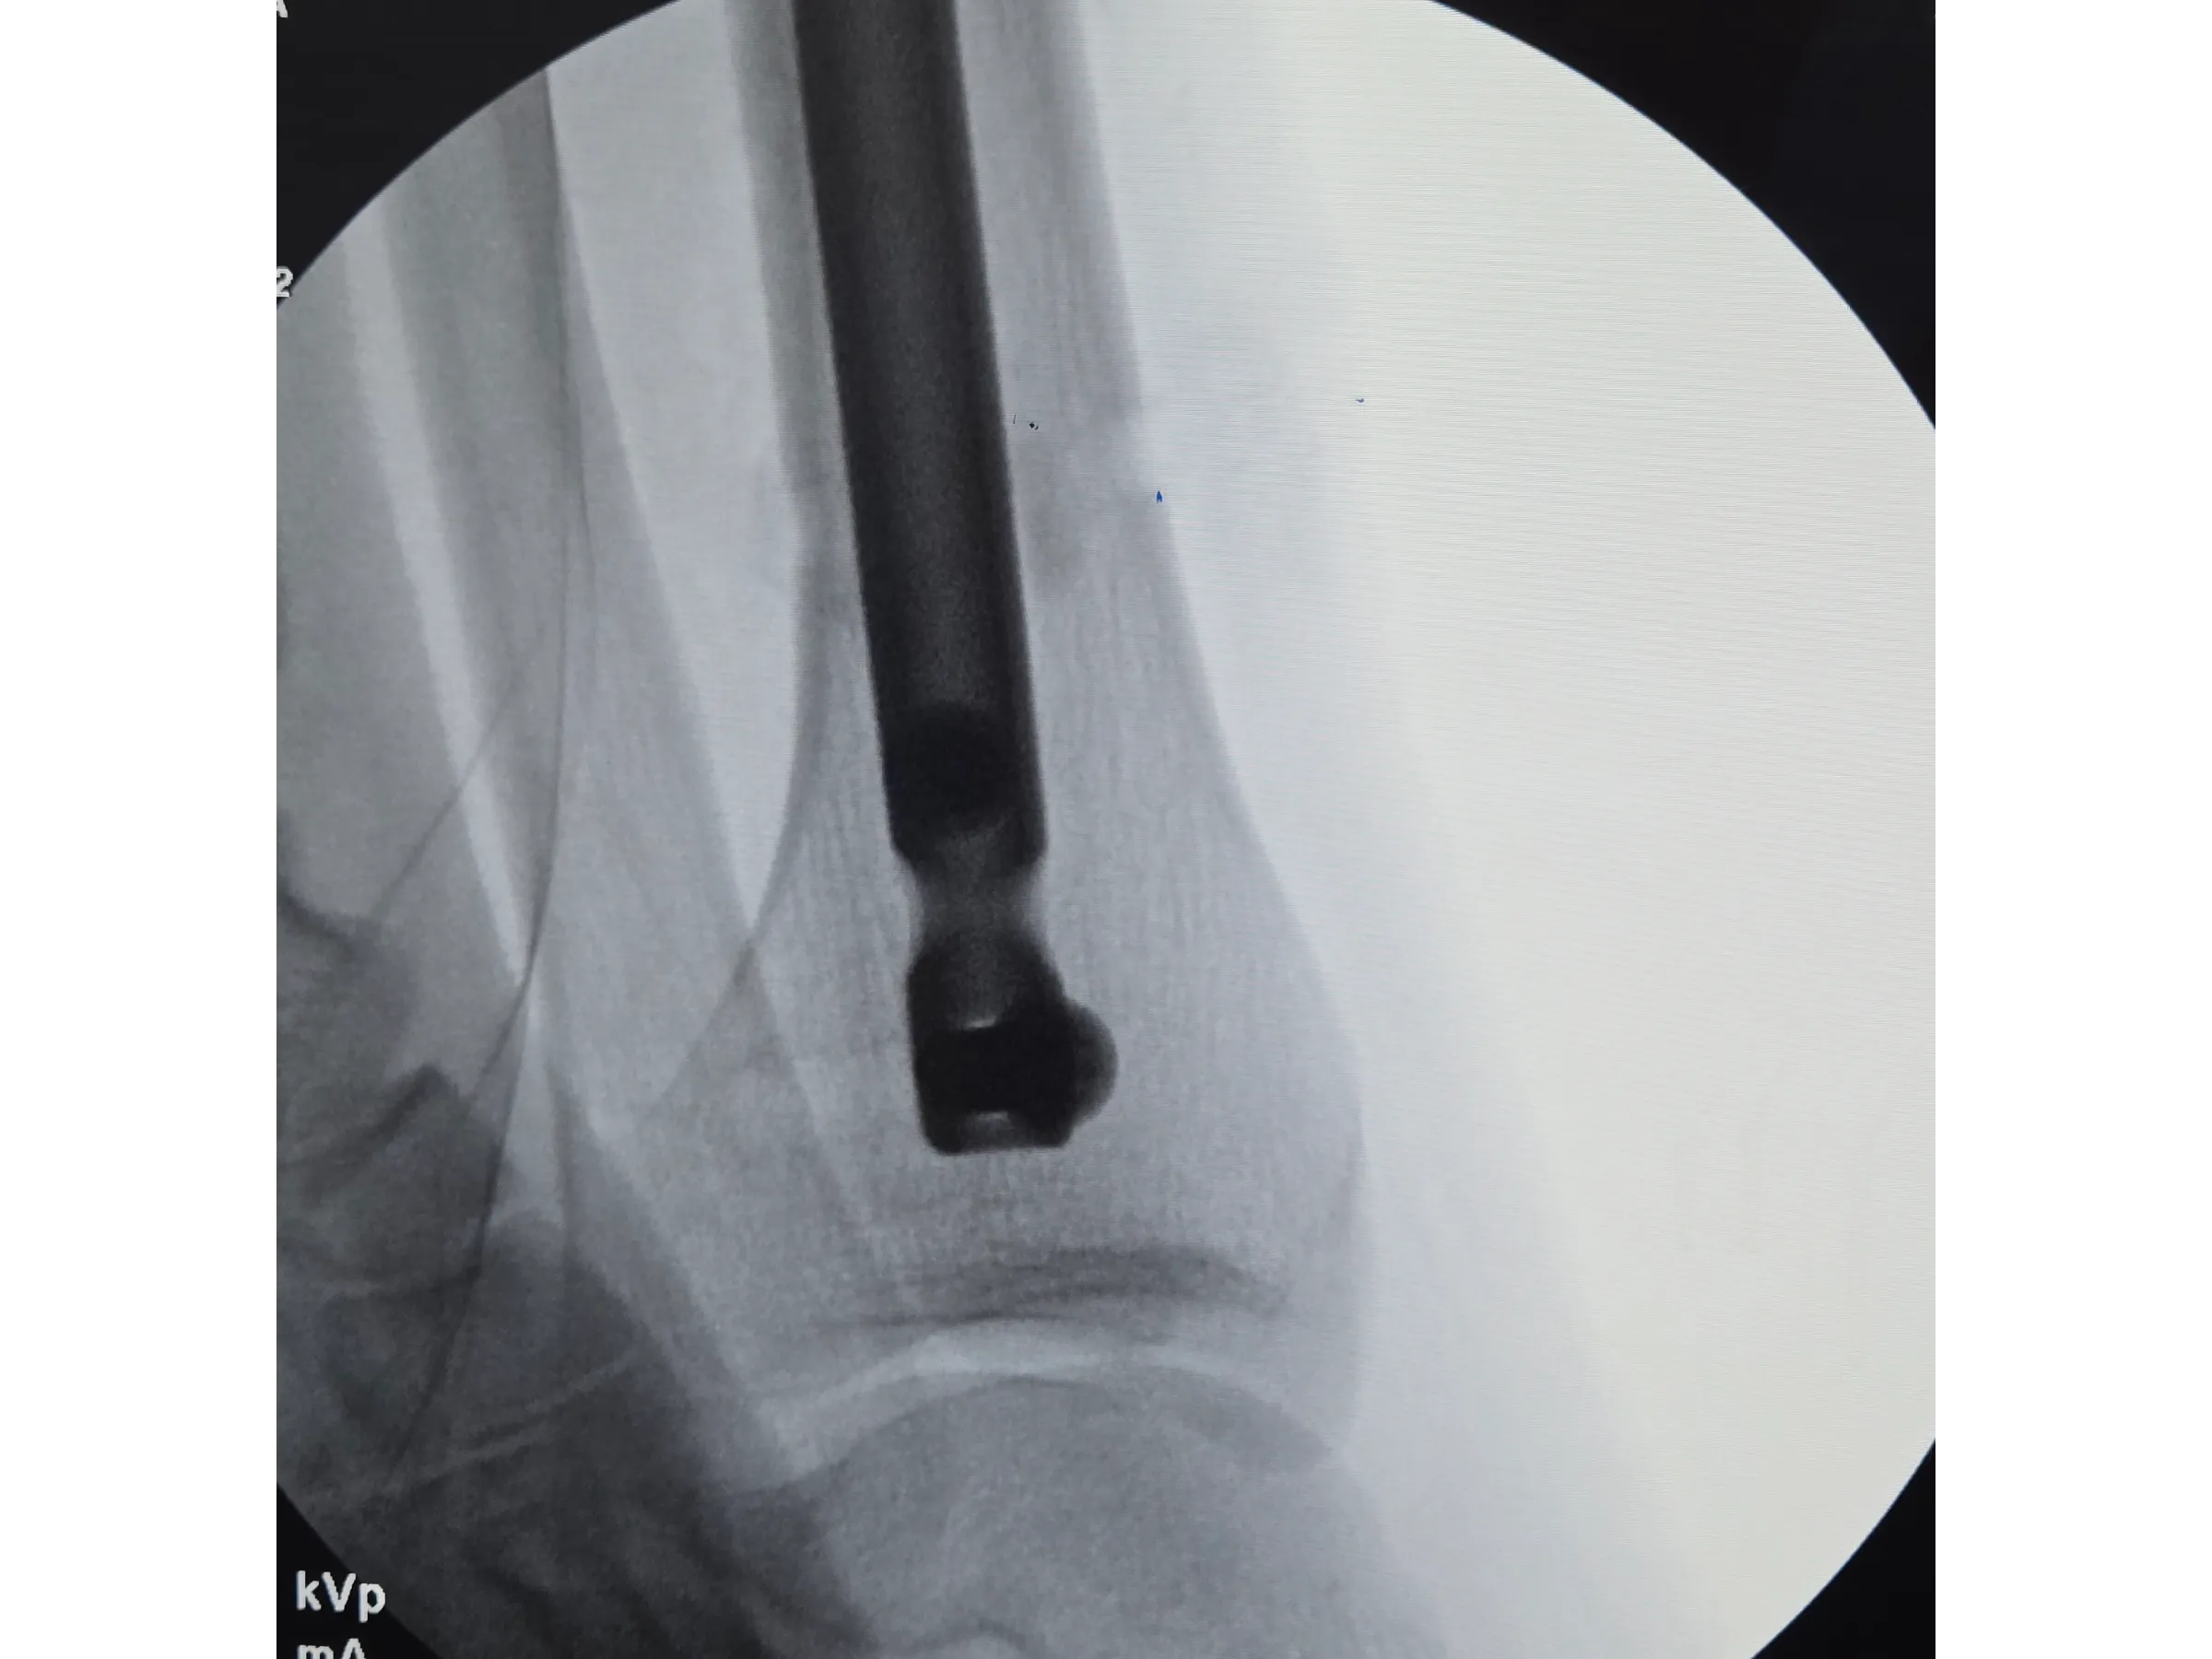

- Introdução segura do fio-guia e fio olivado com controle radiográfico;

- Controle Radiográfico Eficiente: Métodos para evitar direcionamento posterior do fio-guia e garantir centralização do fio olivado;

- Inserção da Haste com Estabilidade: Técnicas para evitar proeminência, garantir avanço adequado e minimizar trauma na retirada do fio olivado;